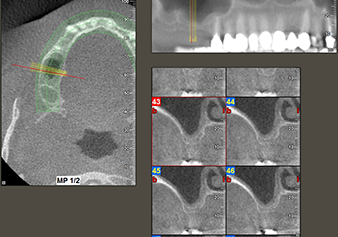

49-летняя пациентка, некурящая и не имеющая ничего примечательного в общей истории болезни, была направлена в нашу хирургическую стоматологическую клинику для хирургического удаления зуба 16 и последующей имплантации. После удаления зуба пациентка перенесла синусит в легкой форме, в результате чего мы сначала выждали шесть месяцев перед проведением операции. Остаточная высота кости при запланированном положении имплантата составляла 3-4 мм (рис. 1 и 2).

Рис.2: ДВТ имеет приемлемые размеры в каждом из аксиальных (слева), латеральных (сверху) и поперечных видов (справа).